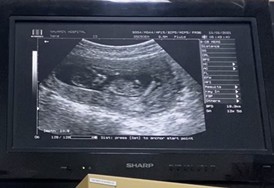

13วีค3วัน หมอยังไม่ดูเพศให้เลยคะ

บ้านนี้ 12week / รู้เพศตอน 4เดือนจ้าาา